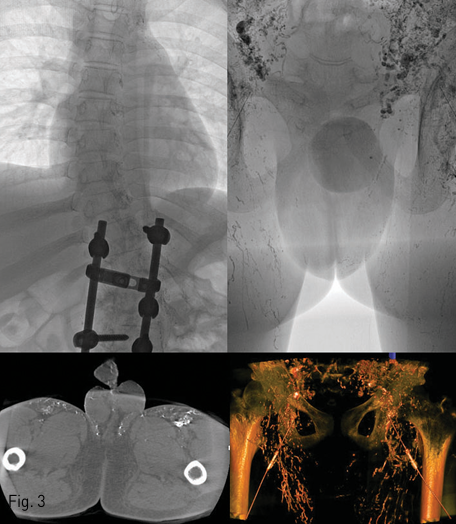

Fig 3

(Top) Bilateral inguinal intranodal lymphangiography using Lipiodol was successfully performed. Venous return via the thoracic duct was intact. However, the lymphatic vessels in the inguinal and pelvic area showed abnormally hyperactive peristaltic movement. In addition, the reversed flow of Lipiodol from the inguinal lymph node to the skin of both medial thigh and scrotum was also noted (dotted circle). (Bottom) However, no large lympho-urethral fistula which can be directly embolized or surgically resected was detected even in the cone-beam CT examination.

MRI T2 강조 영상에서 서혜부 림프절 및 림프관과 골반 내 장골동맥 주변 림프관의 비대 소견을 보였다 (Fig. 2). 양측 서혜부 림프절 경유 리피오돌 림프조영술에서도 상기 비대소견이 있었으나 이에 더하여 허벅지의 안쪽 및 음낭 쪽을 향하는 비정상적인 림프액의 역류가 보였다. 한편 흉관 및 좌측 쇄골하정맥으로의 림프액의 합류는 정상이었다. Spot radiography 및 C-arm CT를 이용하여 주입된 리피오돌의 분포를 정밀하게 관찰하였으나 전립선 요도에서부터 음경 요도에 이르기까지의 범위에서 비정상적인 요도-림프관 연결을 의심할 만한 소견은 보이지 않았다 (Fig. 3). 주입된 리피오돌은 음낭 피부를 거쳐서 귀두 부근의 피부 및 피하조직에 분포하고 있었다. 임상 및 검사 소견을 고려하여 누난증후군과 연관된 림프계 형성이상으로 인해 소장에서 생성된 유미 림프액이 하지, 서혜부, 음낭 피부 방향으로 역류하면서 발생한 림프부종이 있고, 압력이 높아진 림프관내 림프액이 요도로 배액되는 것 으로 진단하였다.